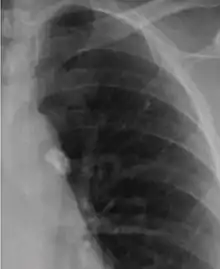

It is a small area of granulomatous inflammation, only detectable by chest X-ray if it calcifies or grows substantially (see tuberculosis radiology).[2] Typically these will heal, but in some cases, especially in immunosuppressed patients, it will progress to miliary tuberculosis (so named due to the granulomas resembling millet seeds on a chest X-ray).[2]

Ghon focus.